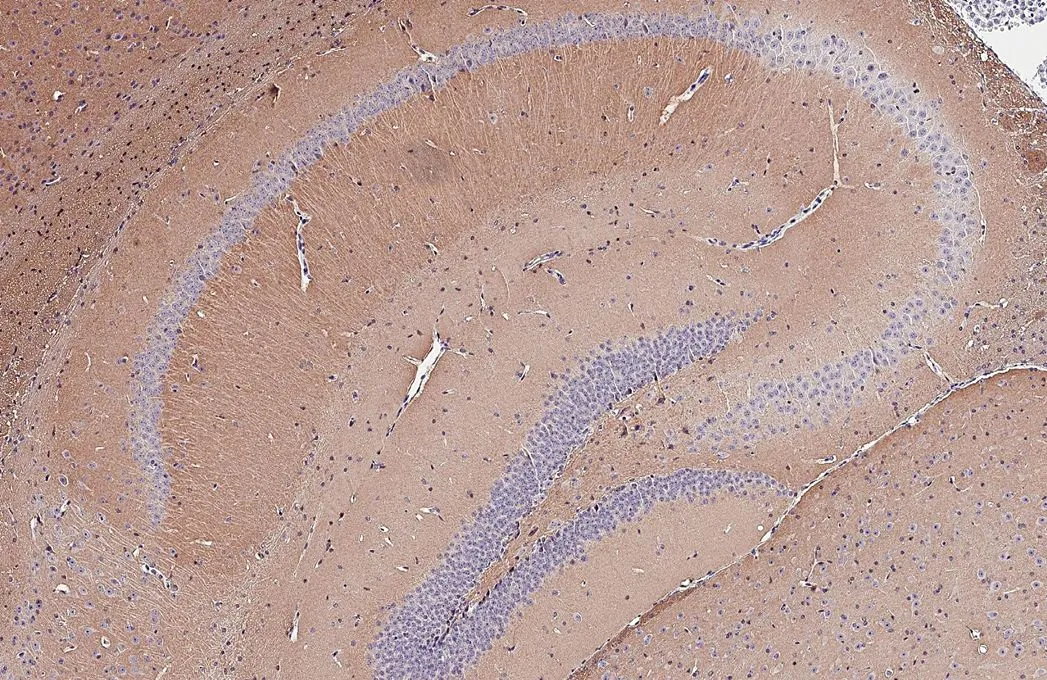

![BASP1 antibody [HL3760] detects BASP1 protein by immunohistochemical analysis. Sample: Paraffin-embedded mouse hippocampus. BASP1 stained by BASP1 antibody [HL3760] (GTX641959) diluted at 1:250. Antigen Retrieval: Citrate buffer, pH 6.0, 15 min BASP1 antibody [HL3760] detects BASP1 protein by immunohistochemical analysis. Sample: Paraffin-embedded mouse hippocampus. BASP1 stained by BASP1 antibody [HL3760] (GTX641959) diluted at 1:250. Antigen Retrieval: Citrate buffer, pH 6.0, 15 min](https://www.genetex.com/upload/website/prouct_img/normal/GTX641959/GTX641959_T-45670_20250529_IHC-P_M_2_25061003_198.webp)